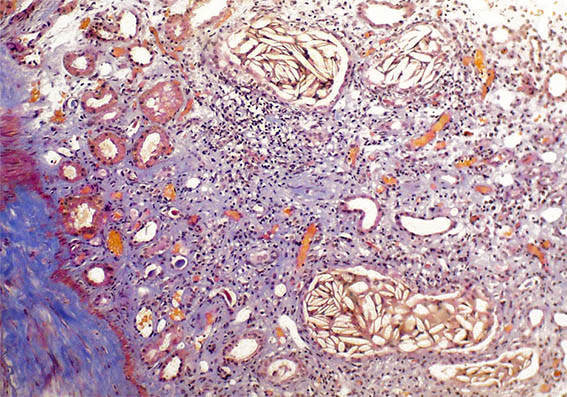

Figure 3. H&E, X400. Areas with marked interstitial inflammation and tubular damage.